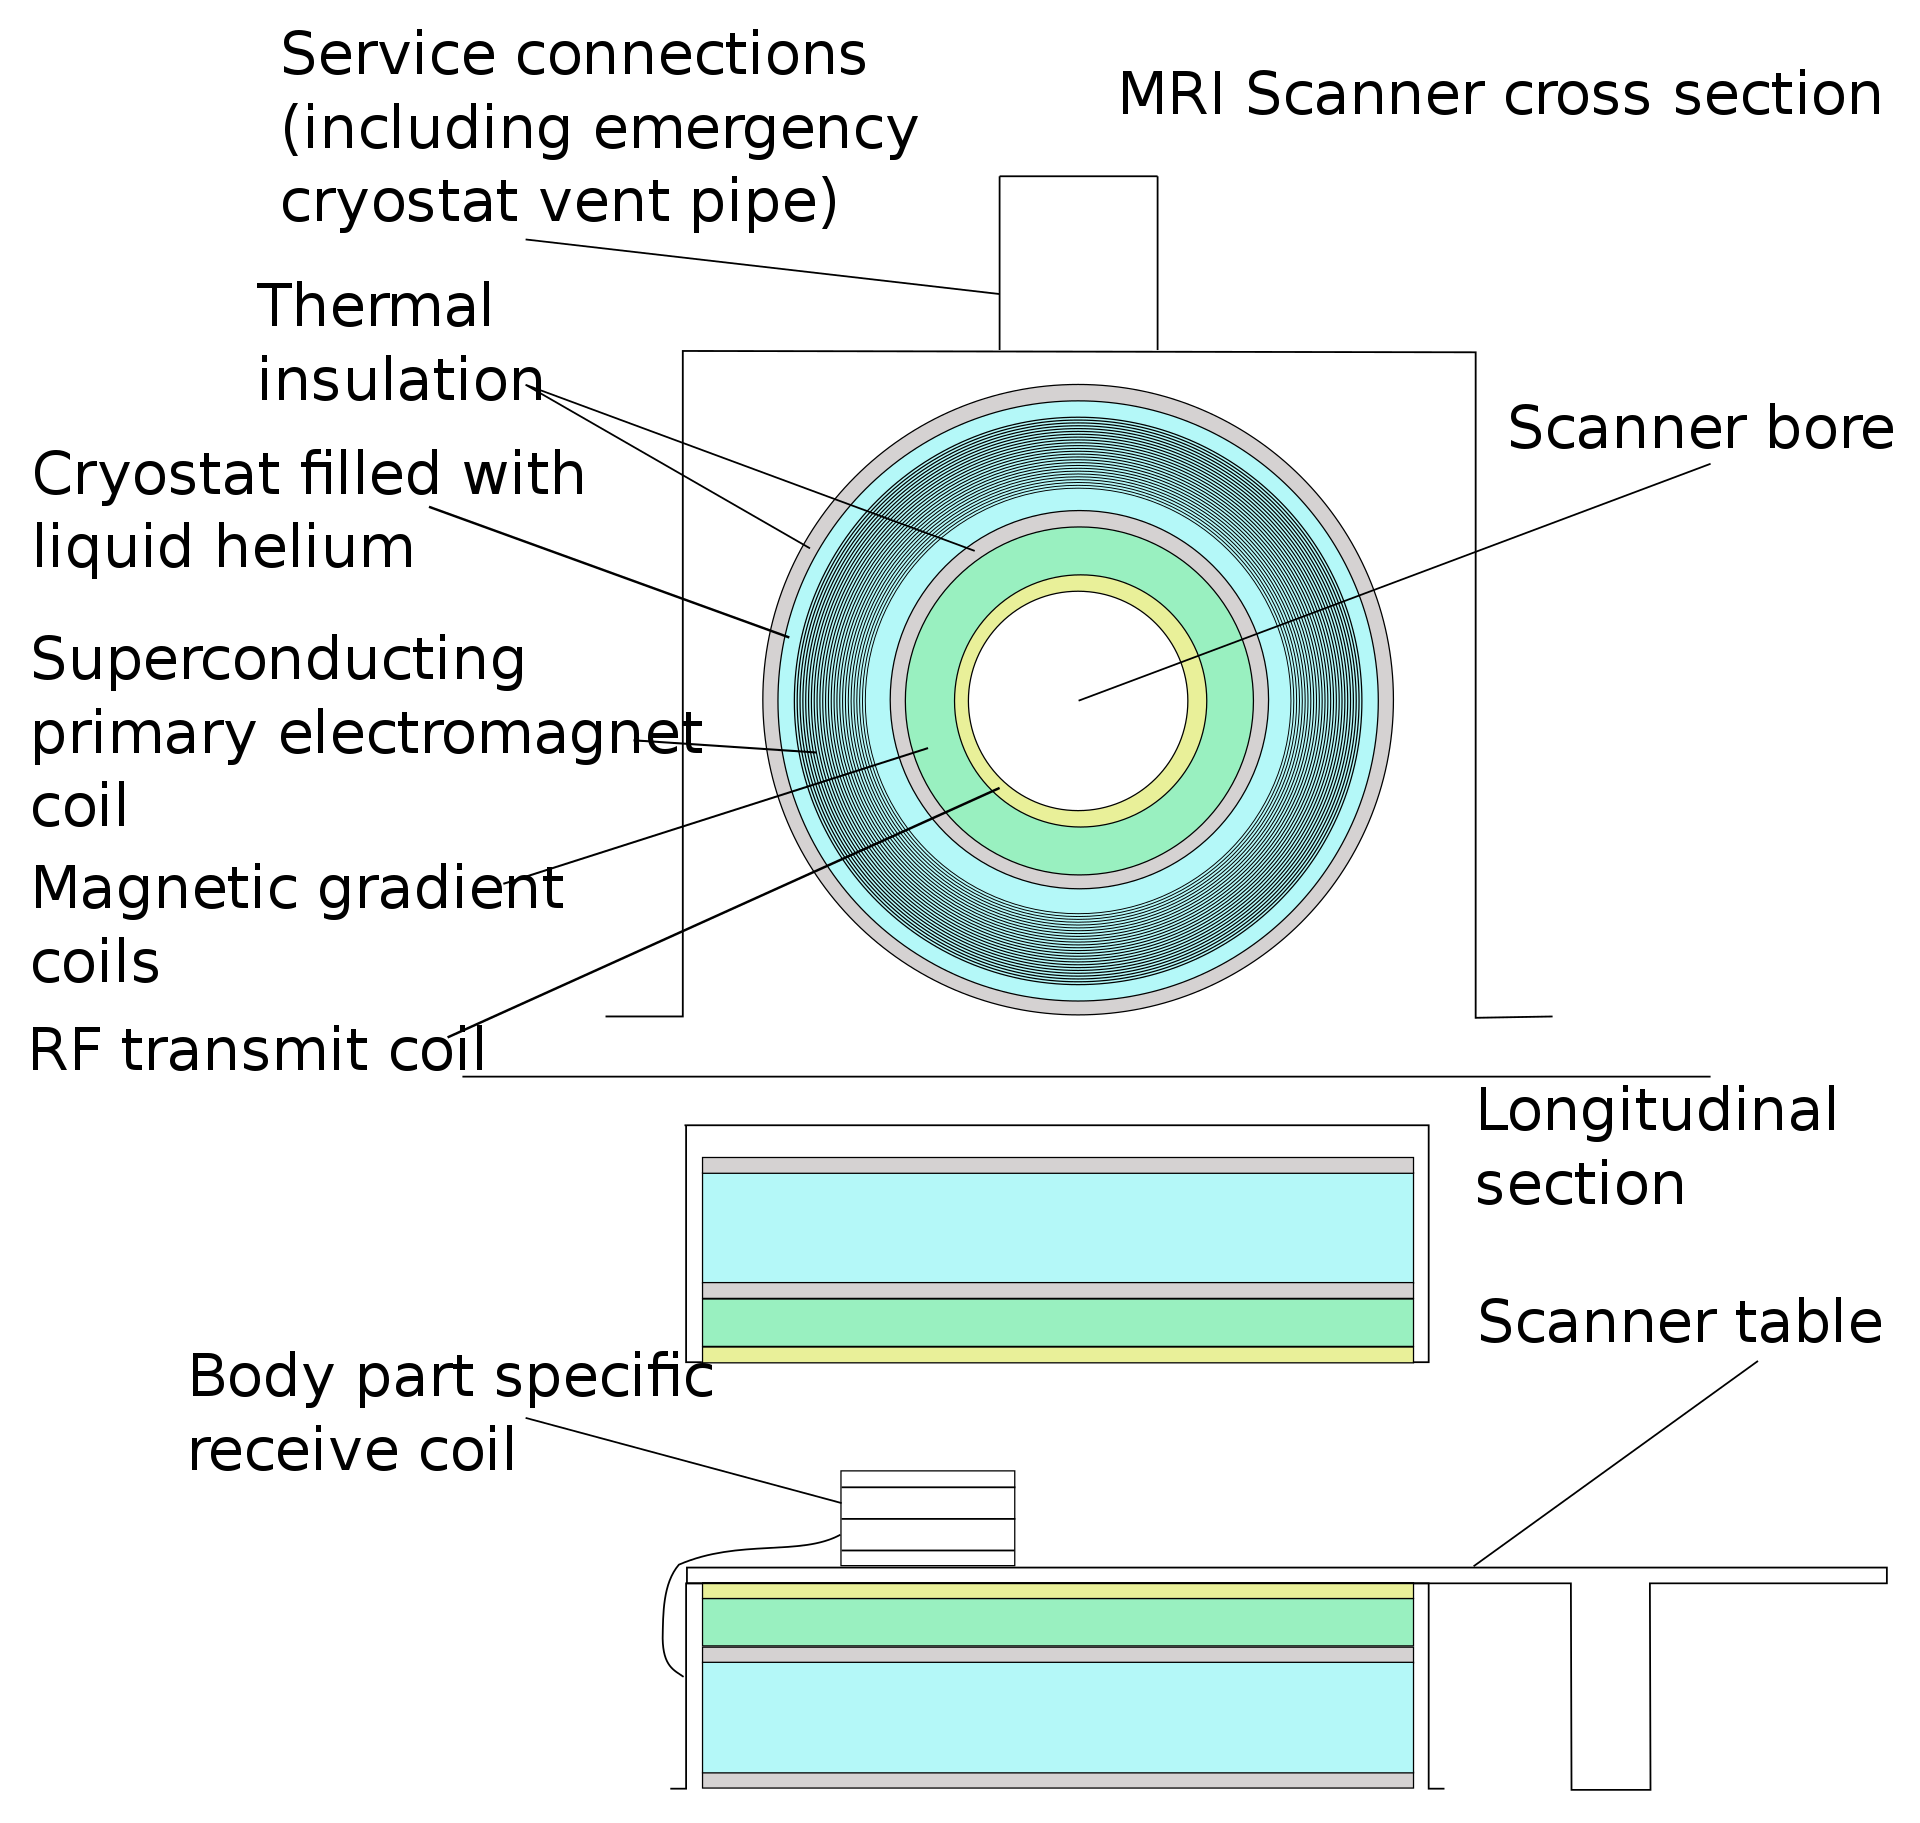

成像原理

MRI通过对静磁场中的人体施加某种特定频率的射频脉冲,使人体中的氢质子受到激励而发生磁共振现象。停止脉冲后,质子在弛豫过程中产生MR信号。通过对MR信号的接收、空间编码和图像重建等处理过程,即产生MR信号。

核磁共振成像原理:原子核带有正电,许多元素的原子核,如1H、19FT和31P等进行自旋运动。通常情况下,原子核自旋轴的排列是无规律的,但将其置于外加磁场中时,核自旋空间取向从无序向有序过渡。自旋的核同时也以自旋轴和外加磁场的向量方向的夹角绕外加磁场向量旋进,这种旋进叫做拉莫尔旋进,就像旋转的陀螺在地球的重力下的转动。自旋系统的磁化矢量由零逐渐增长,当系统达到平衡时,磁化强度达到稳定值。如果此时核自旋系统受到外界作用,如一定频率的射频激发原子核即可引起共振效应。这样,自旋核还要在射频方向上旋进,这种叠加的旋进状态叫做章动。在射频脉冲停止后,自旋系统已激化的原子核,不能维持这种状态,将回复到磁场中原来的排列状态,同时释放出微弱的能量,成为射电信号,把这许多信号检出,并使之能进行空间分辨,就得到运动中原子核分布图像。原子核从激化的状态回复到平衡排列状态的过程叫弛豫过程。它所需的时间叫弛豫时间。弛豫时间有两种即T1和T2,T1为自旋-点阵或纵向驰豫时间,T2为自旋-自旋或横向弛豫时间。